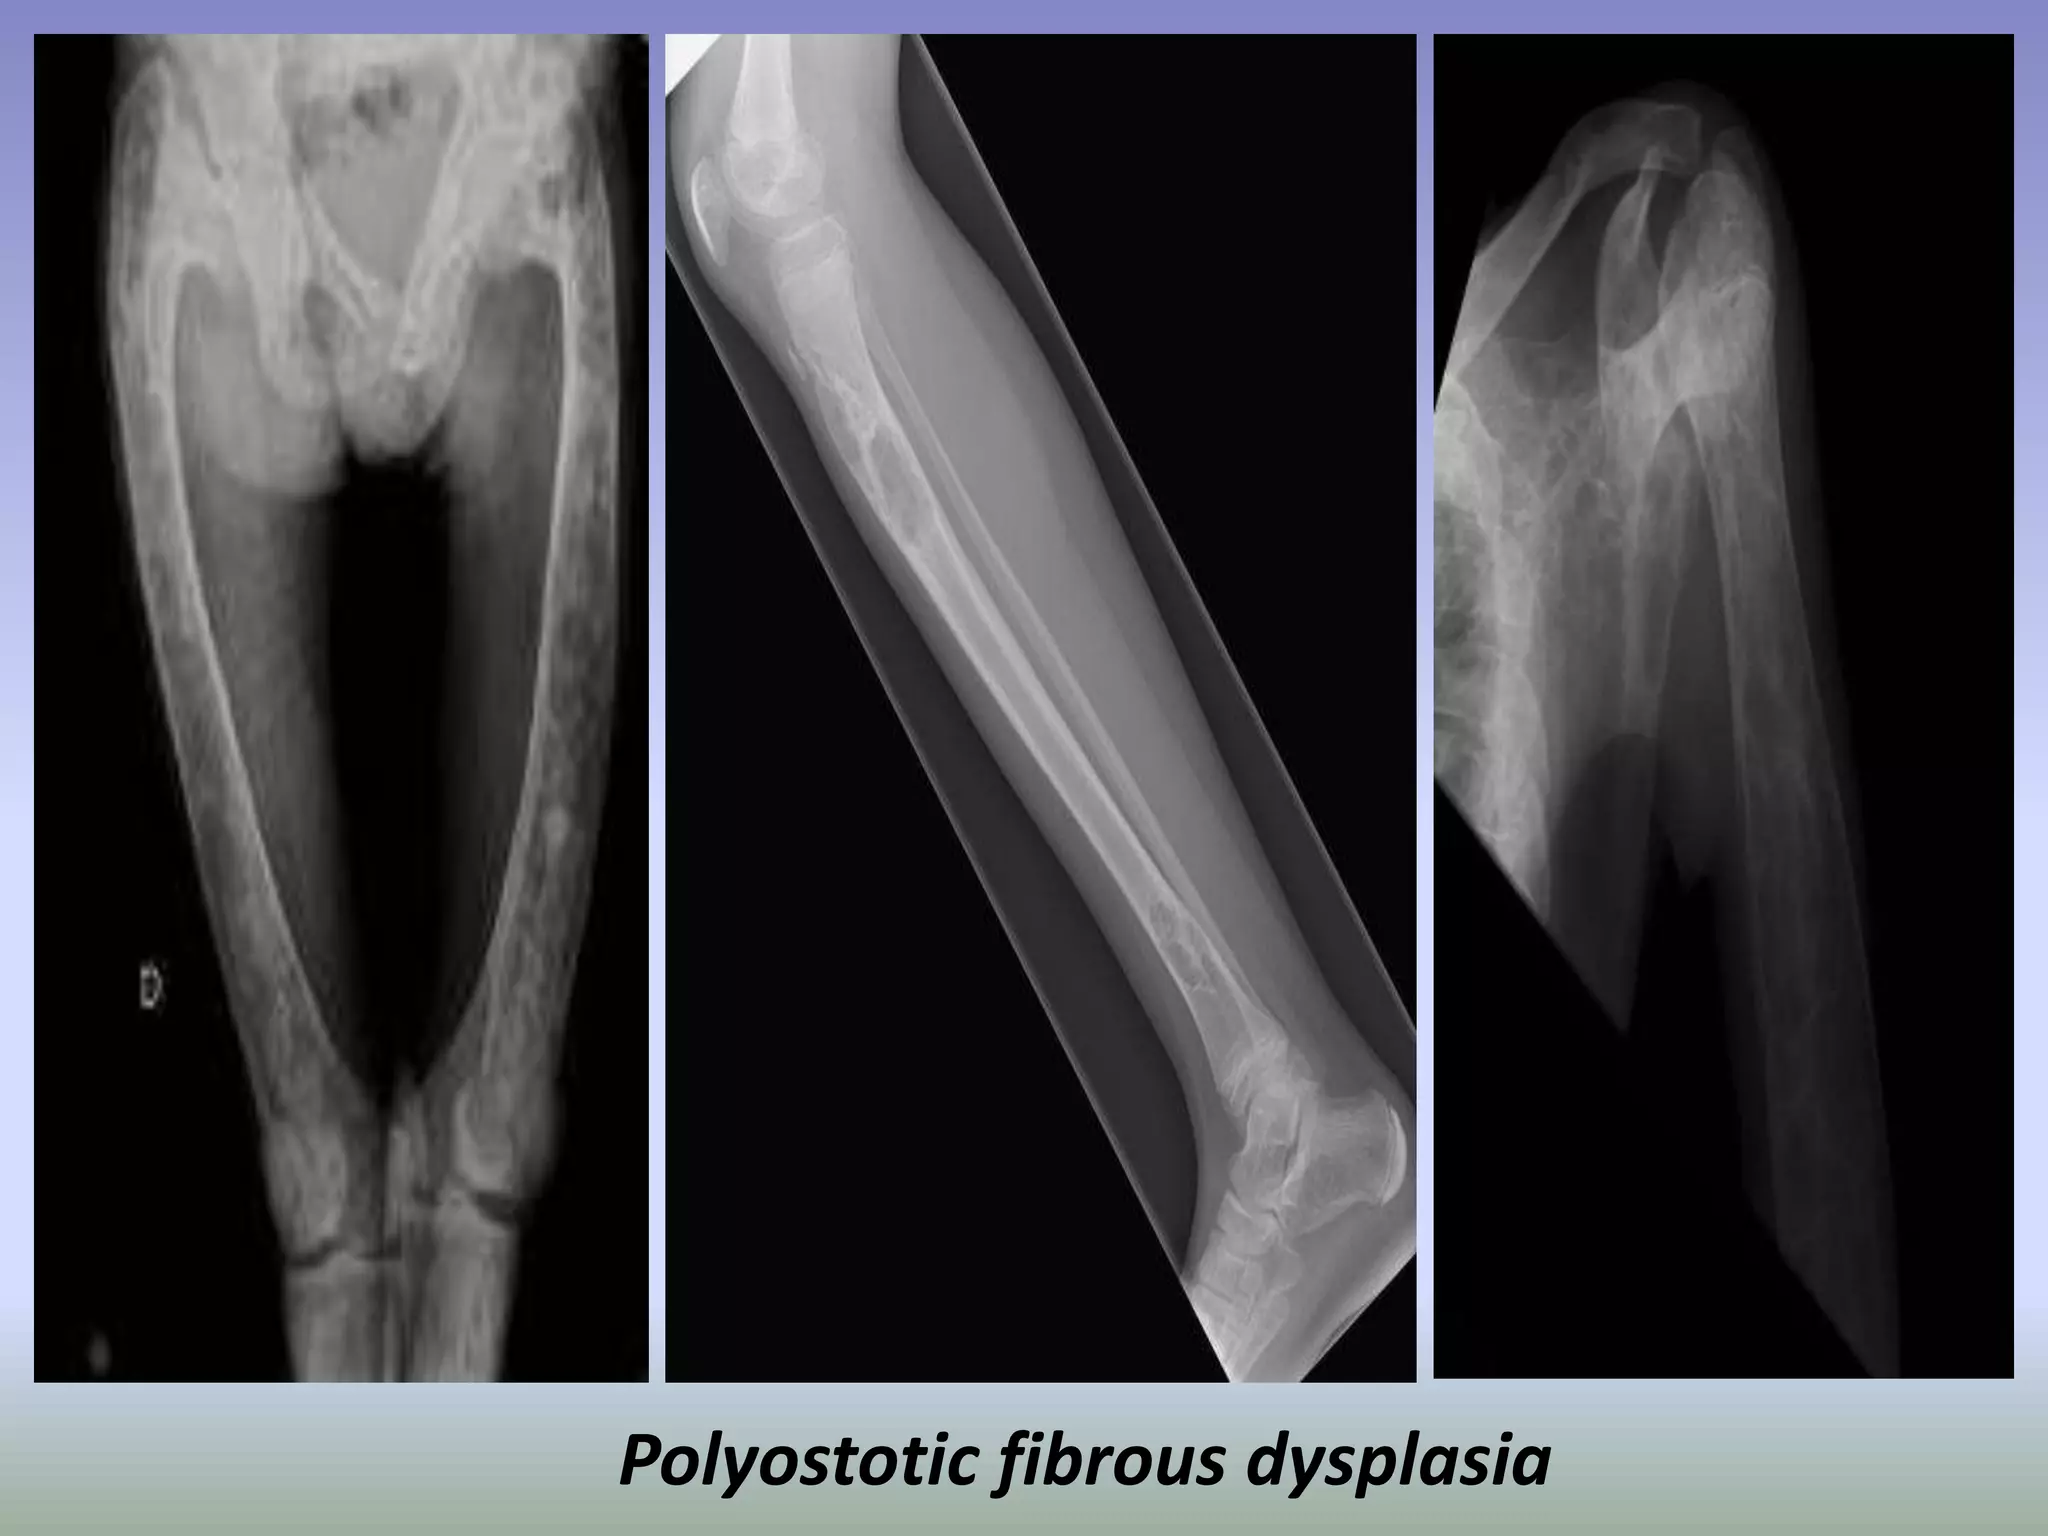

Polyostotic fibrous dysplasia.

Polyostotic fibrous dysplasia

Fibrous dysplasia.